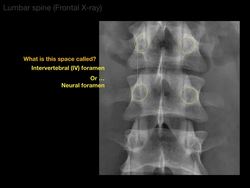

The Noted Anatomist

Anatomy of a Lumbar x-ray

This video tutorial presents the anatomy of a lumbar x-ray: 0:00. Introduction 0:44. Counting lumbar vertebrae 1:54. Front view (lumbar spine) 6:03. Front view (lumbar spine) 9:10. Front view (lumbar spine) 11:46. Acknowledgements